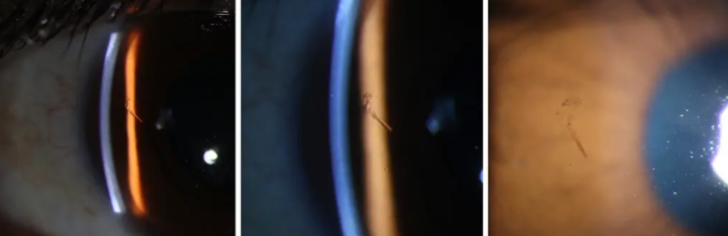

Amerika Birleşik Devletleri'nin Michigan eyaletinin Detroit bölgesinde Kresge Göz Enstitüsü'nde yapılan araştırmaya göre, Bostonlu olduğu sanılan 30'lu yaşlarındaki kimliği belirsiz bir adamın 15 yılı aşkın süredir gözüne saplanan 3 milimetrelik tahta kıymığıyla yaşadığı söylenedi. Detroit'teki Harvard Tıp Fakültesi ve Wayne State Üniversitesi'nden doktorların hastanın gözüne ait paylaştığı görseller kısa sürede dikkatleri çekti.

Daily Mail'in haberine göre adam, 15 yıl önce bahçeyle uğraşırken gözüne bir şeyin battığını ancak semptomların geçmesi üzerine durumu ciddiye almadığını söyledi.